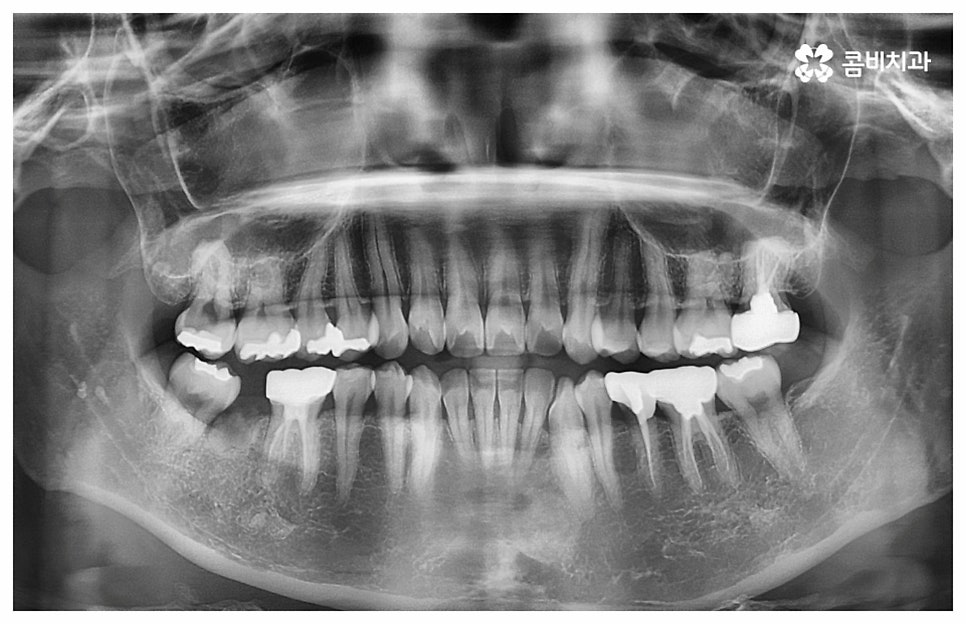

즉 중장년기에는 이미 골격이 완성된 상태이기 때문에 치아 이동 속도가 느려서 청소년기에 교정을 시작하는 것보다 전체 치료 기간이 조금 더 오래 걸릴 수 있으나 치아 교정이 아예 불가능한 것은 아니기 때문에 하고 싶다는 생각이 든다면 먼저 치과에 내원하셔서 자신의 상황에 대해 꼼꼼하게 검진부터 받아 보시길 권유드리고 있어요. 이때 3D CT 와 같은 정밀 검진 장비를 갖춘 치과라면 더욱 편안한 마음으로 검진 및 상담에 임하실 수 있을 거예요.

나이가 들어가면서 치아와 주위 조직들이 약해질 수 있고 치주 질환이 발생할 위험도 높아지기 때문에 중년치아교정 치료시 환자분들의 상황에 따른 맞춤 진료를 더욱 세심하게 진행할 필요가 있어요. 교정 방법이나 주의점에 대해서 꼼꼼하게 확인하고 계획을 세워야 할 뿐 아니라 교정 치료 전에 충치나 잇몸병과 같은 구강 질환이 발견되었다면 이를 미리 깨끗하게 치료하고 진행 과정 중간에도 장치에 음식물 찌꺼기가 끼지 않도록 위생 관리를 철저하게 해주며 치료 후 치아와 잇몸이 약해지지 않도록 환자분들 각각의 치아 이동 속도에 따라 무리하지 않는 것이 중요한 포인트라고 할 수 있습니다.

이때 환자분들에 따라 치열을 가지런하게 만들기 위한 구강 내 공간이 부족하다면 발치를 해야하는 경우도 있는데 혹시 평상시 상용하는 약이 있는 분들은 미리 의료진에게 얘기하고 복용 스케줄을 조절 하시는 게 좋을 거예요. 또한 골다공증이나 관절염, 당뇨 등 만성 질환을 앓고 있는 분들의 경우 치아 이동 속도가 더욱 더딜 수 있으므로 이에 대해서도 충분히 인지하실 필요가 있어요.

위 사진은 환자분의 동의를 받아 이해를 돕기 위한

사진이며, 실제 치료 결과는 다를 수 있습니다.